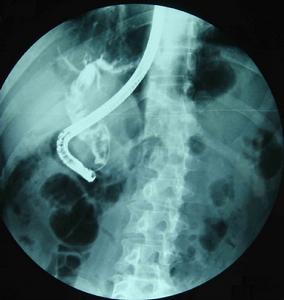

5.ERCP和PTC检查均可清晰显示胆管系统的全貌,能比较准确提供肝内外胆管和胆囊结石的大小、数量、位置以及肝内外胆管扩张、狭窄等病理改变状况,是获得术前准确诊断最重要的检查方法。ERCP基本无创、并发症较少,PTC为有创、并发症稍多,可根据病人和病变的具体情况选择。一般情况下多选择ERCP检查。